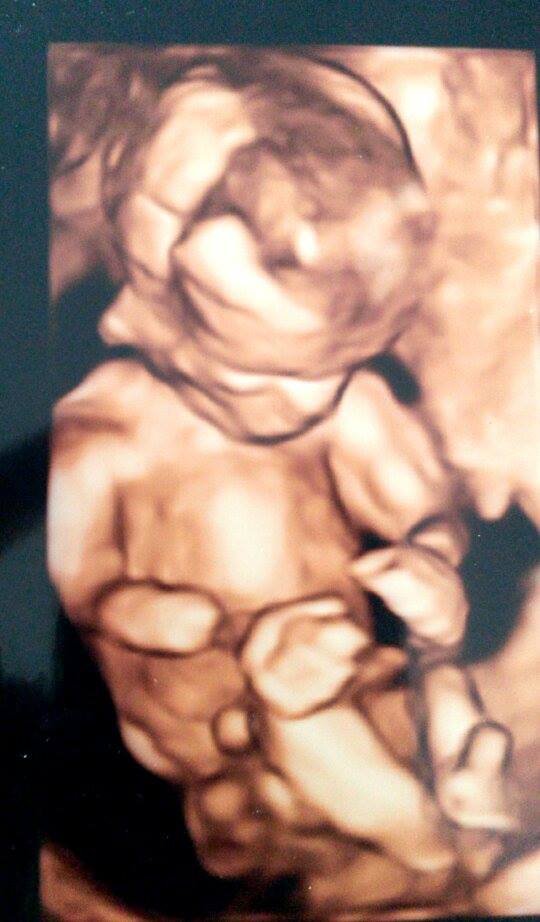

Podstoupila jsem Screening v 1. trimestru, který je placený a cena se liší, pruměrně se pohybuje od 1000- 1500Kč a zjišťuje se jestli miminko nemá nějaký rozštěp, jestli má ručičky, nožičky, proště kompletně vše a také ještě jestli nebude mít Downův syndrom. Naštěstí nám vše vyšlo dobře.